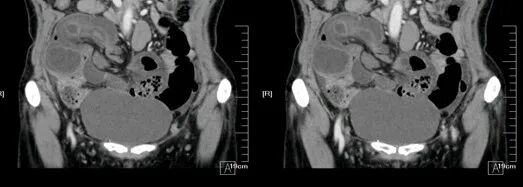

升结肠癌并广泛转移

气腹管怎么接肠梗阻、肠套叠、气腹、肝挫伤、脾挫伤、肾挫伤、胰腺损伤、食管癌、胃肠肿瘤_https://www.jmylbn.com_新闻资讯_第49张

气腹管怎么接肠梗阻、肠套叠、气腹、肝挫伤、脾挫伤、肾挫伤、胰腺损伤、食管癌、胃肠肿瘤_https://www.jmylbn.com_新闻资讯_第50张

升结肠癌

气腹管怎么接肠梗阻、肠套叠、气腹、肝挫伤、脾挫伤、肾挫伤、胰腺损伤、食管癌、胃肠肿瘤_https://www.jmylbn.com_新闻资讯_第51张

气腹管怎么接肠梗阻、肠套叠、气腹、肝挫伤、脾挫伤、肾挫伤、胰腺损伤、食管癌、胃肠肿瘤_https://www.jmylbn.com_新闻资讯_第52张

升结肠癌并肝转移